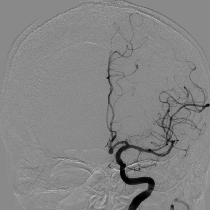

もやもや病

頭蓋内血管の閉塞がみられます。血管造影では血管が閉塞し、周囲に「もやもや病」がみられます。

バイパス手術によって血管が頭蓋骨を通り、皮膚の太い血管と脳をつなげて治療します。

もやもや病のMRA画像

血管造影検査の画像

バイパス術後のCTA画像